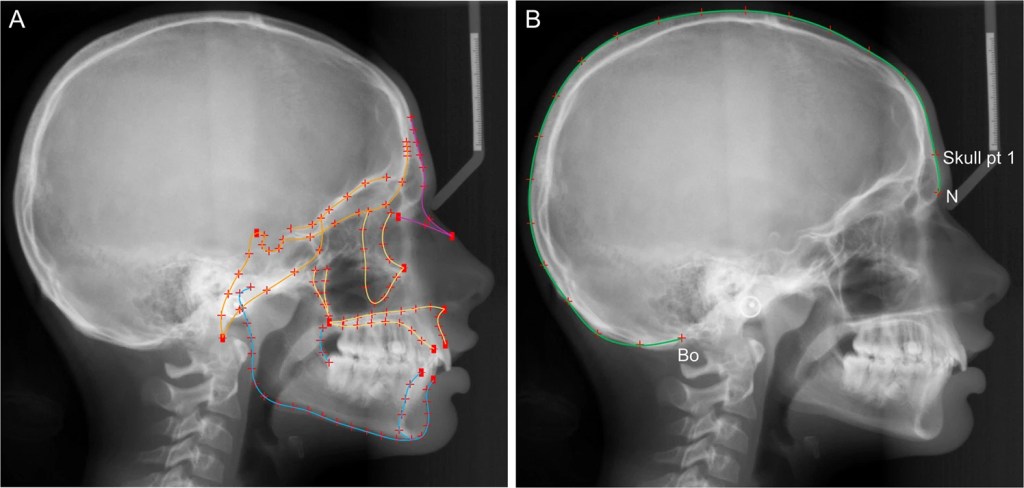

El Dr. Stansfield señala que el desarrollo de la mandíbula parece estar influenciado más por su uso que por la genética. Para comprobarlo, su equipo utiliza modelos biomecánicos para analizar cómo las fuerzas de masticación han cambiado con el tiempo y cómo estos cambios continúan en la actualidad.

Los estudios muestran que la ausencia de estos dientes varía entre poblaciones. En África, la frecuencia de agenesia M3 es relativamente baja, mientras que en algunas regiones de Asia, incluyendo Japón, India, Turquía, Israel e Irak, la incidencia es más alta. La relación entre el tamaño de los molares y la agenesia M3 sugiere que la reducción en el tamaño de los dientes podría ser un factor clave en esta transformación evolutiva.